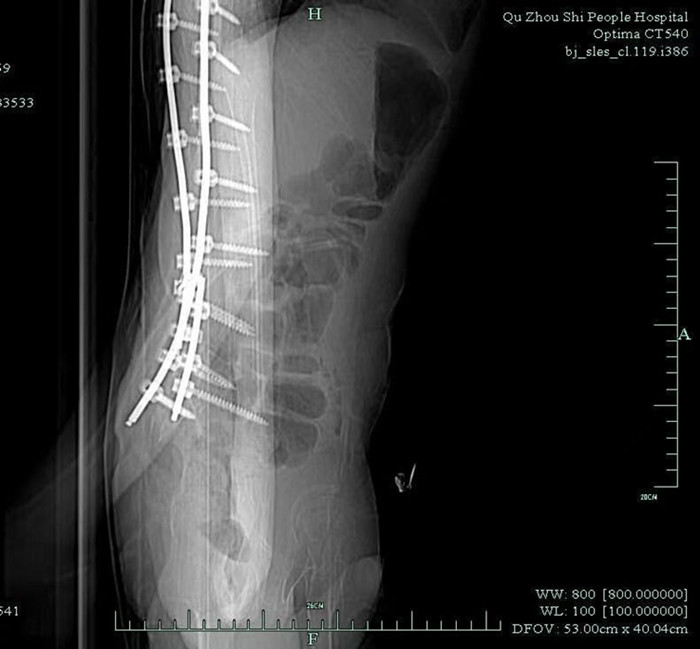

早就收過病危通知書的小徐,由于沒有肌肉力量的支撐,大部分骨骼被擠壓變形。體重不足40公斤的他,幾年前因?yàn)榧怪鶄?cè)彎,靠著打進(jìn)身體里的37枚鋼釘,才勉強(qiáng)能在輪椅上坐穩(wěn)。

鞘內(nèi)注射是神經(jīng)內(nèi)科醫(yī)生的基本操作,本身并沒有多大難度。但由于小徐長(zhǎng)年疾病導(dǎo)致脊椎側(cè)彎,椎管變得彎彎曲曲,還有37根鋼釘橫亙其中,這讓原本并不復(fù)雜的注射治療變得十分困難。